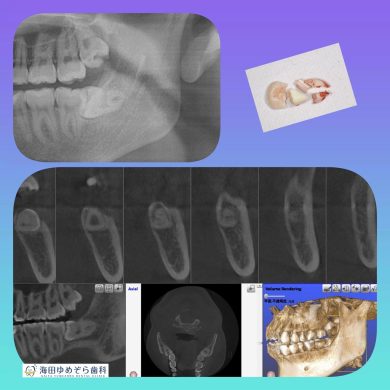

横向き親知らずの抜歯症例

院長はこのような横向きに埋まっている抜歯ケースも

1000症例以上の手術実績あり☆

横に埋まっている場合はCT撮影で安心です☆